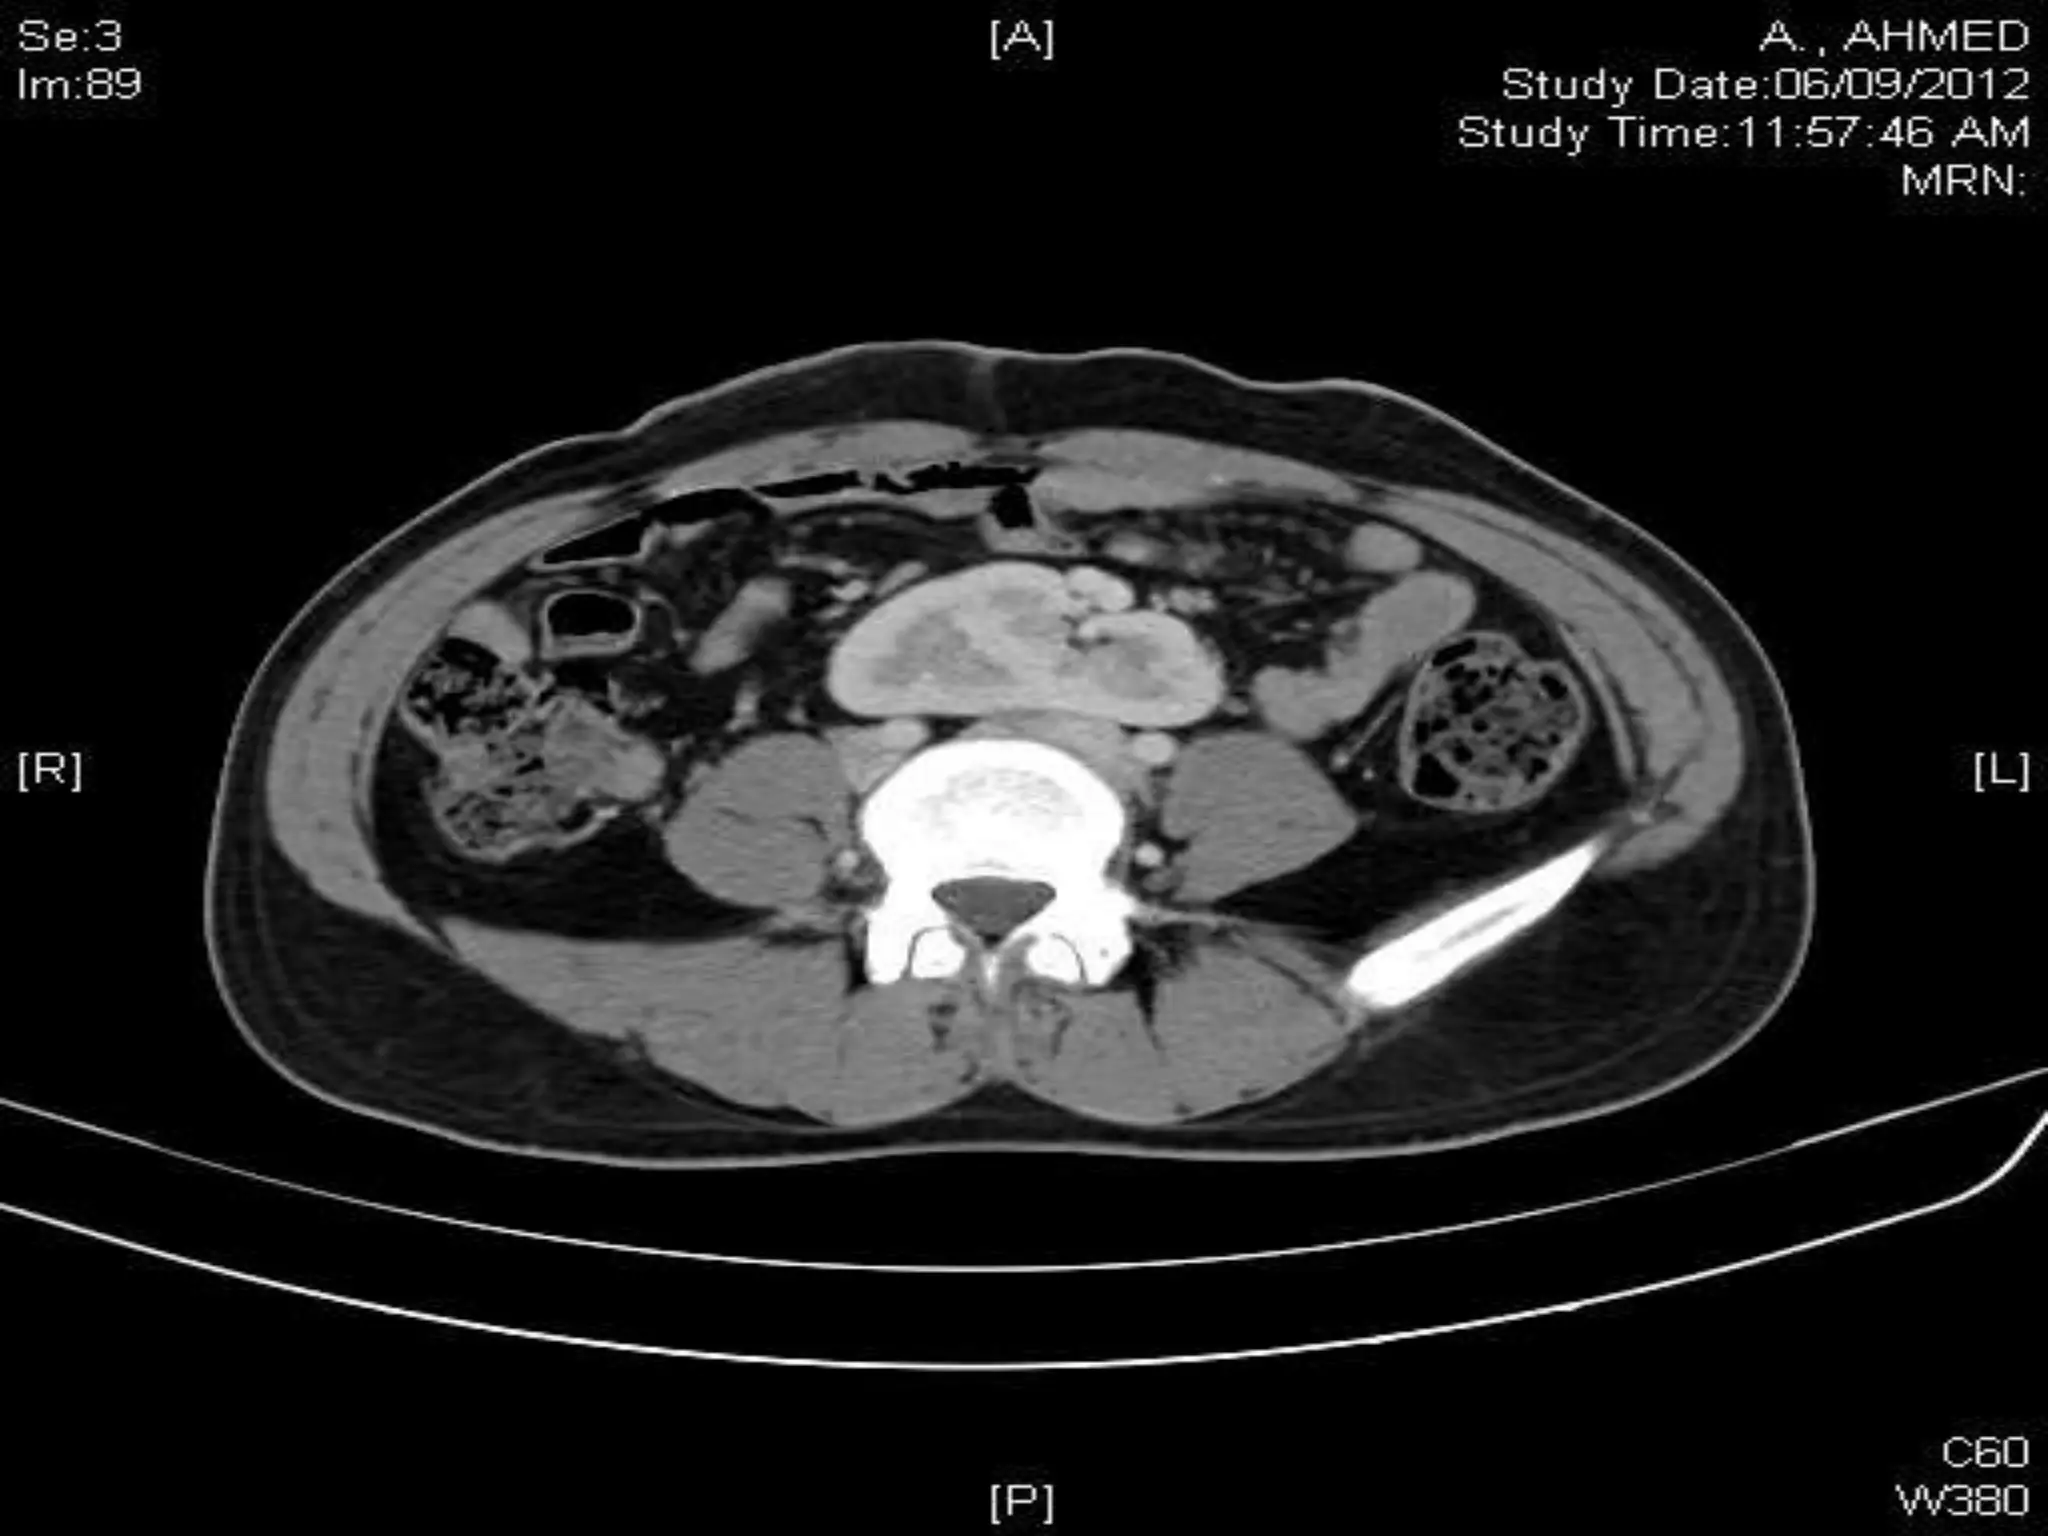

CHALLENGES IN RPLND

Retroperitoneal lymph node dissection kaushal